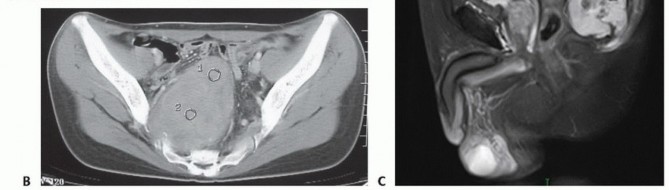

التصوير المقطعي المحوسب والرنين المغناطيسي

- التصوير المقطعي المحوسب (CT): يُعد بتقنية التباين الوريدي الأسلوب الأمثل لتقييم مدى انتشار الورم في العظم وتدميره، والتكلسات المحتملة، والموقع التشريحي، والإمداد الدموي، وعلاقة الورم بالأعضاء الحشوية. يساعد في التفريق بين الأورام الحميدة والخبيثة.

- التصوير بالرنين المغناطيسي (MRI): بتقنية التباين، يُعد حاسمًا لتصوير الأنسجة الرخوة ومدى انتشار الورم فيها، وعلاقته بالأنسجة المحيطة (مثل الأوعية الدموية والأعصاب والعضلات والأعضاء الحشوية). يُعتبر الأسلوب الأمثل لتصوير الأنسجة الرخوة نظرًا لقدرته الفائقة على التمييز مقارنةً بالتصوير المقطعي.